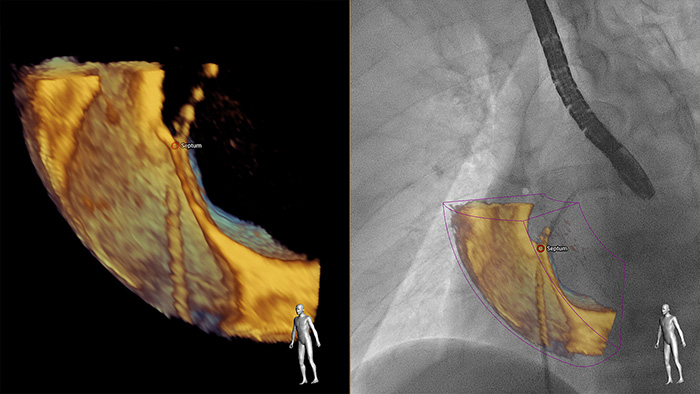

EchoNavigator

Greater insight and confidence in finding and treating the problem through SmartFusion. EchoNavigator automatically fuses live 3D TEE and live X-ray in real time so you can intuitively guide your device in the 3D space more quickly.